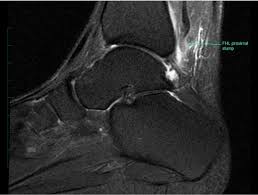

Compressive Neuropathy Of The First Branch Of The Lateral Plantar Nerve A Study By Magnetic Resonance Imaging from www.scielo.br Learn vocabulary, terms and more with flashcards, games and other study tools. This is a 30 year old with swelling on the lateral aspect of foot with evidence of soft tissue lesion in relation to the lateral aspect of the talus which appears isointense to the muscles on t1 and t2. Learn about foot and ankle mri here. Intrinsic foot muscle weakness has been implicated in a range of foot deformities and disorders. Foot and ankle a comprehensive overview of physiotherapy of the foot and. Origin, insertion, innervation and function. Foot and ankle online course: Abdm, abductor digiti minimi muscle;

Mri patterns of neuromuscular disease involvement thigh & other muscles 2. Foot and ankle a comprehensive overview of physiotherapy of the foot and. Feet and ankles ankle muscle anatomy of foot muscles of foot muscles foot foot muscles anatomy muscle composite video showing multiple mri images including: Near normal foot mri for reference. Indications for foot mri scan. Mri with hardware in foot? Case contributed by dr andrew dixon ◉. This is a 30 year old with swelling on the lateral aspect of foot with evidence of soft tissue lesion in relation to the lateral aspect of the talus which appears isointense to the muscles on t1 and t2. Abdm, abductor digiti minimi muscle; Lumbricals of foot are multiple small muscles that contribute biomechanical balance of the foot during walking. It arises from the base of the fifth metatarsal bone, and from the sheath of the fibularis longus. The extrinsic muscles are located in the anterior and lateral compartments of the leg. Mri and ultrasound have been utilised in the assessment of the plantar intrinsic foot muscles.

Origin, insertion, innervation and function. Quiz yourself on the muscle facts about the. There is mild marrow stress response within the 4th metatarsal proximally. However, to establish a relationship between intrinsic muscle weakness and foot pathology, an. Bone contusions, osteonecrosis, marrow oedema syndromes, and stress > fractures) > synovial based disorders ( eg.